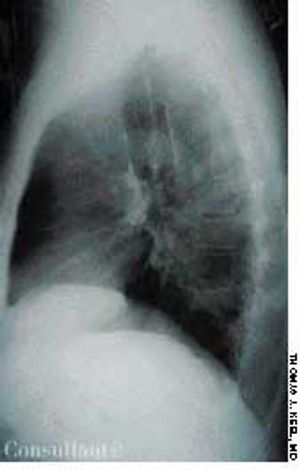

After 6 weeks of persistent low back pain, an overweight 72-year-old woman sought medical evaluation. There was no history of trauma.